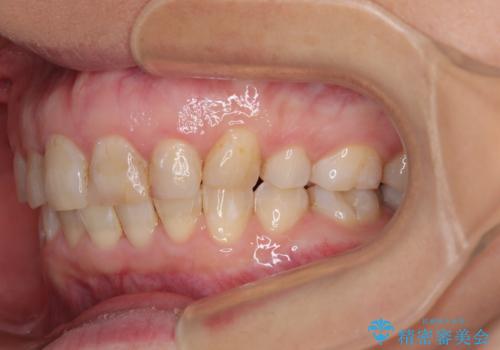

- 前歯のデコボコと前方に斜めに飛び出した前歯を気にして来院された患者様です。

口元の突出感はあまり気になっていませんでしたが、上下の前歯の前後差が大きかったため、上顎左右の第一小臼歯を抜歯し、上顎が裏側装置であるハーフリンガルにて矯正治療を行うこととしました。